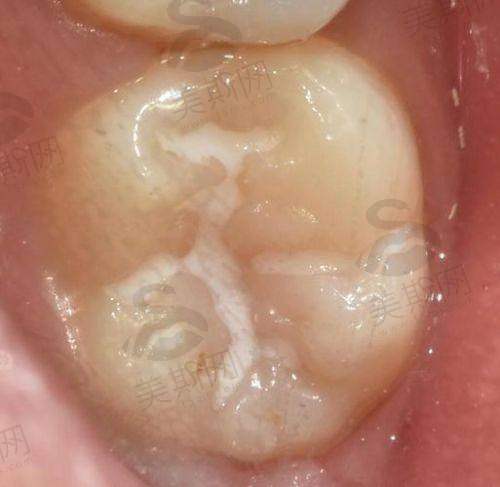

综合齿科:包括树脂补牙(采用高强度纳米树脂)、智齿拔除(支持微创拔除阻生齿)、活动义齿修复等基础项目。

7. 乐美口腔树脂补牙(3M纳米树脂):380元/颗起